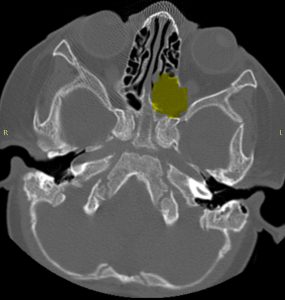

CT-ul efectuat imediat postoperator a confirmat ablația macroscopic completă (fig 2)

Figura 2: imagini CT comparative preop-postop la finalul interventiei chirurgicale